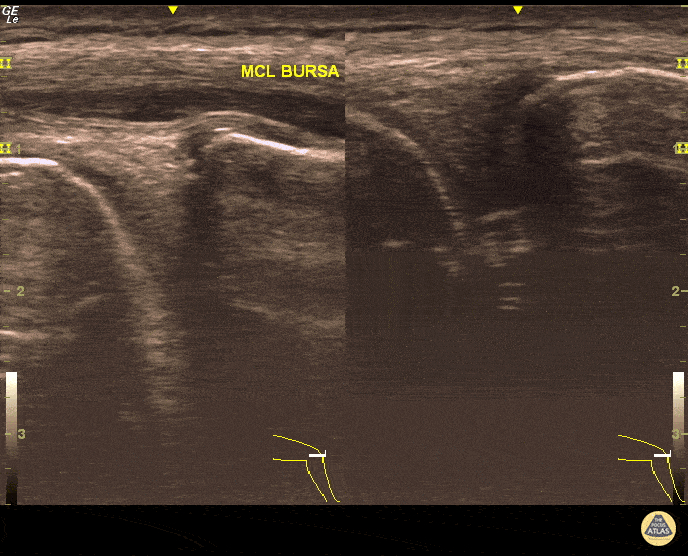

Musculoskeletal - MCL Bursitis

29 year-old elite level soccer player with medial knee pain. He describes this being 'the worst episode ever', as he was having recurrent episodes of such pain. Valgus and flexion deformity due to prior surgery 15 years ago at the affected knee. Sharp, non-radiating pain 9/10 on NPRS, wakes him up at night. Palpation of medial knee and valgus stress test positive. Concomitant recent trauma. Unable to train/compete. USG of his knee revealed both MCL insertional edema (grade 1 injury) and MCL bursitis. Guided aspiration (3cc) and corticosteroid injection to MCL bursae revealed excellent outcomes. He returned to play 3 days later. Pitfall: It was not an MCL injury. Key point : Intervention was necessary and US-guidance allowed correct needle positioning without complication. Dr. Omer Batin Gozubuyuk, Sports Medicine Specialist, Istanbul University, Istanbul, Turkey.